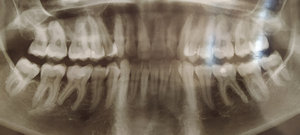

Для установления брекетов врач мне рекомендует удалить верхнюю справа четверку, чтобы поставить на ее место клык, и нижний второй резец справа, аргументируя тем, что так будет быстрее идти лечение, по словам врача корень у этого резца оголен и подвижен (хотя я не чувствую, чтобы он шевелился) и, что все равно в дальнейшем этот зуб я потеряю (и никто, кроме стоматологов не будет замечать, что резцов нижних у меня 3, вместо 4х).

Правда ли то, что этот зуб (резец второй) не здоров? И лучше удалить его, а не 4 нижнюю справа?

Разве нагрузка будет правильно распределена, если справа внизу останется два премоляра, а вверху один?

По снимку невозможно диагностировать подвижность зуба. Существует методика, при которой возможно удаление и всех восьмых зубов, и, если потребуется, четверок.